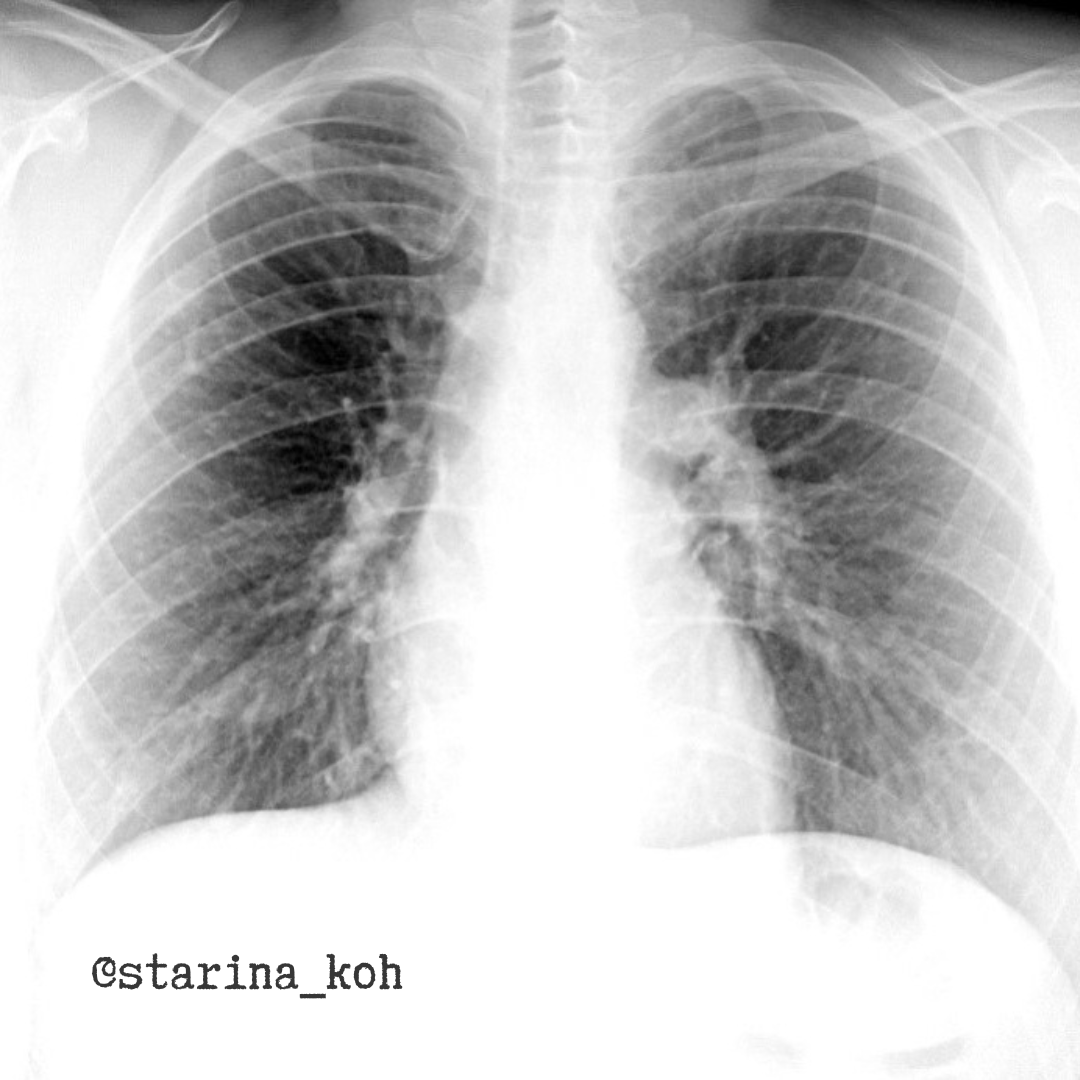

Нашу коллегу-терапевта, красивую молодую девушку ничто бы не беспокоило, если бы эти фтизиатры (хехе) не придумали свои профилактические осмотры с НДКТ, где в легких выявили не совсем типичные для туберкулеза очаги. На самом деле, подозрительный очаг можно выявить и на флюорографии - присмотритесь, он помечен стрелкой.

Так вот, после НДКТ у пациентки очаг был трактован как артериовенозная мальформация (АВМ). Можно встретить также название ангиомы или фистулы. Доказать подобную аномалию развития можно только при введении контрастного препарата и убедиться, что в легком есть своеобразные "клубочки", в которых отсутствует капиллярное русло, а кровь напрямую сбрасывается из системы легочной артерии в вены.

И мы сделали такое исследование - обнаружили, что такие "клубочки" активно заполняются контрастом уже в артериальную фазу. При внимательном рассмотрении исследовании мы выявили, что в легких присутствует далеко не одна такая АВМ - а нашли их целых 4 штуки - разной формы и размеров - с обеих сторон. При нативном исследовании в сторону АВМ можно подумать также проанализировав сосуды, подходящие к данному очагу в/д справа - он не соответствует нормальному калибру сосудов данной зоны.

К слову сказать, такие небольшие АВМ не вызывают никакой клинической симптоматики, но доказать их природу было необходимо, особенно у медицинского работника - чтобы в дальнейшим не возникало вопросов на проф. осмотрах. Формирование таких АВМ - порок эмбрионального развития сосудов и может сочетаться с другими пороками сердца. В ряде случаев такие фистулы обнаруживают не только в легких, но и в других органах (например, в печени и на коже - в рамках синдрома Рендю-Ослера-Вебера). Клинически значимы как правило только крупные фистулы, при которых происходит массивный сброс крови в обход капилляров, что приводит к гипоксии, появлению одышки, обмороков и т.д. При наличии клинической симптоматики производят хирургическое лечение - эмболизацию АВМ либо удаление сегмента с ней.